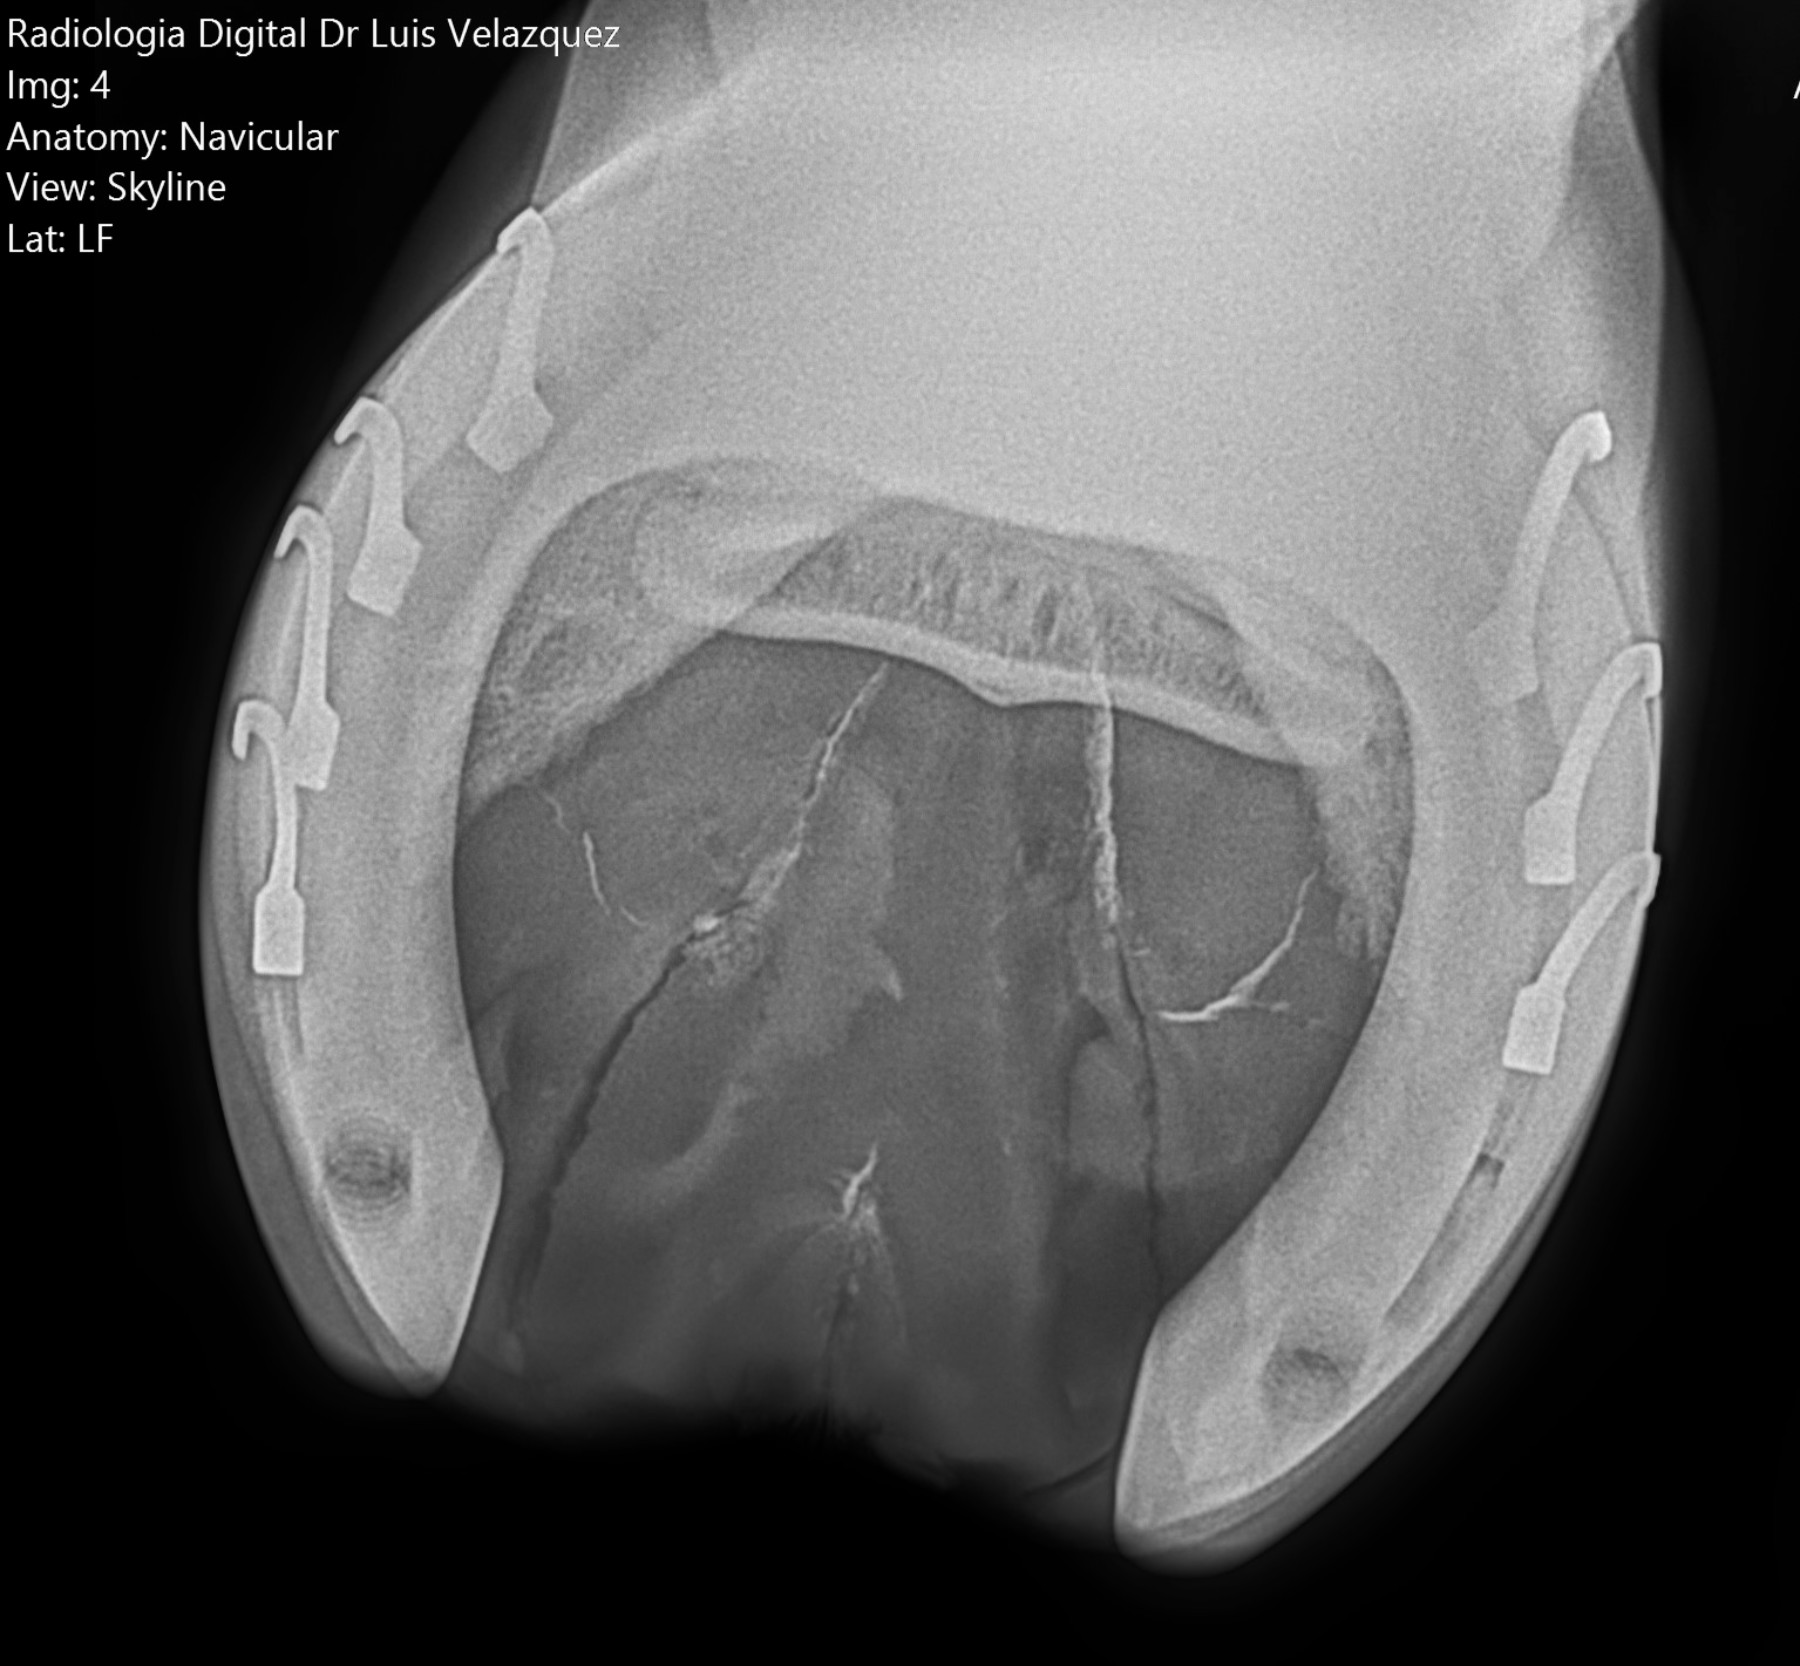

Cambios Térmicos en las Extremidades de Caballos,

Asociados a Golpes y su Evaluación por Termografía.

Los caballos de salto, en competencia, pueden derribar obstáculos y lastimarse. Si se golpean, no siempre claudican. Considerando al calor como un signo de inflamación, se evaluaron los cambios térmicos de 6 áreas de las extremidades torácicas y pelvianas de 23 caballos de salto en nivel de competencia de 1.05 a 1.60 m de altura, por medio de termografía durante 4 días de competencia (N=2208 áreas).